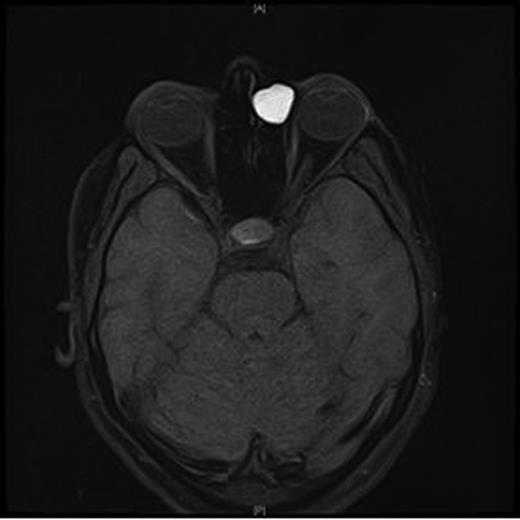

A CT scan of the paranasal sinuses and orbits revealed the cystic expansile 1.6 cm mass at the left medial canthus to be of soft tissue density. The lateral wall of the mass expanded outwards into the orbit (suggesting an anterior ethmoidal mucocele) rather than being pushed medially (which could have been indicative of a dacryocystocele) (Fig. 4).